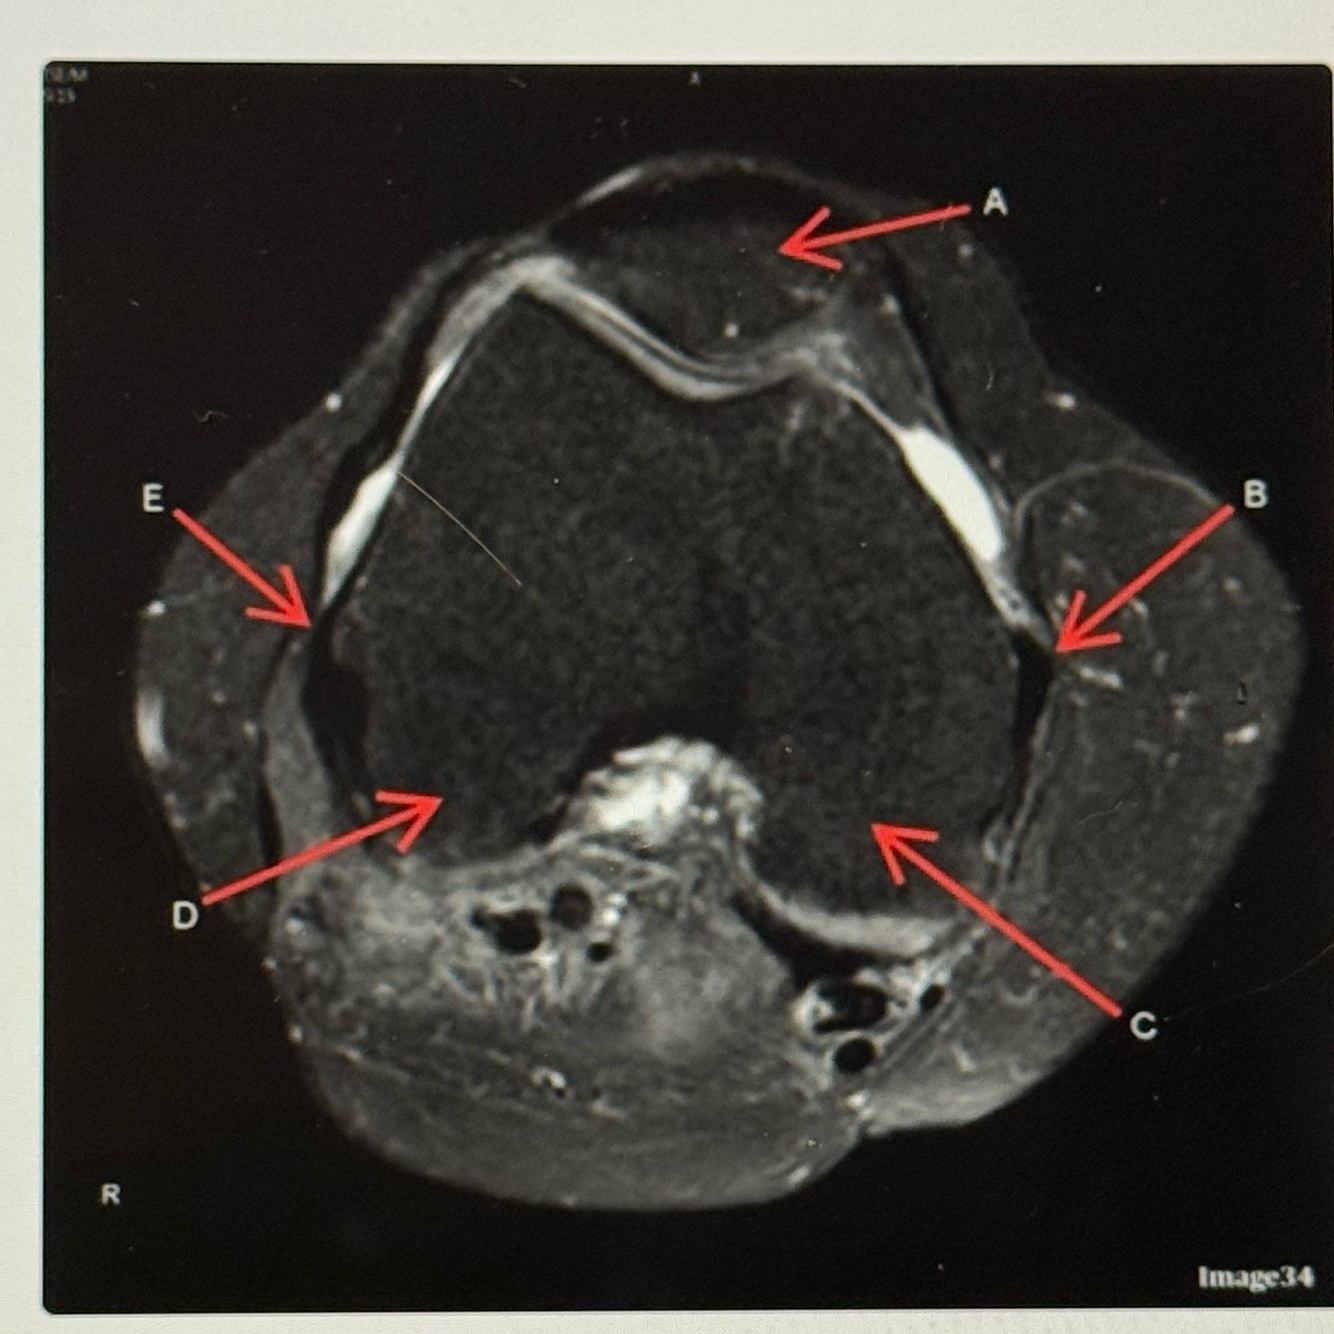

Letter A points to the

Letter B points to the

A

Medial

Collateral ligament (MCL)

Q

Letter E points to the

Lateral collateral ligament (LCL)